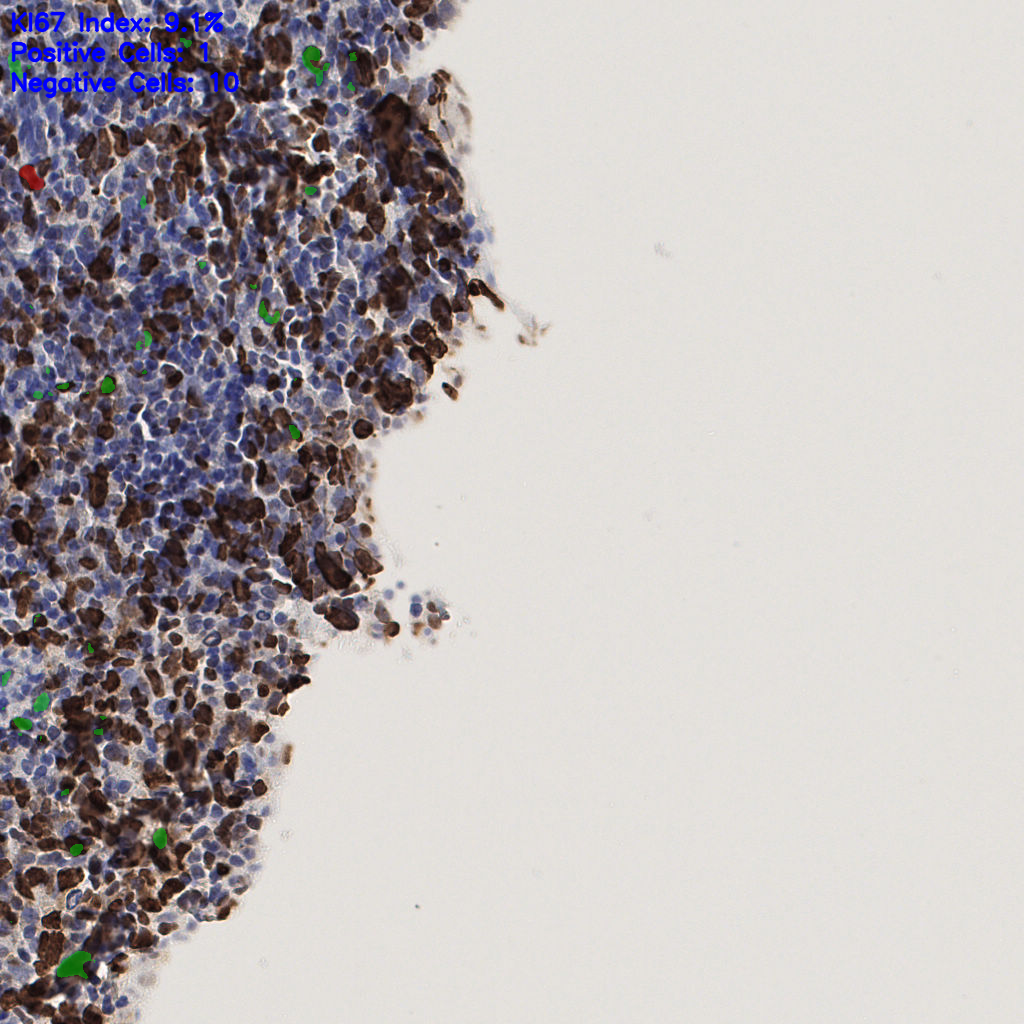

7.85%

Ki67 指数

阴 1104

阳 94

切片统计

总切片

1953

有效

288

已标记

有效率

15%

标记后

标记前